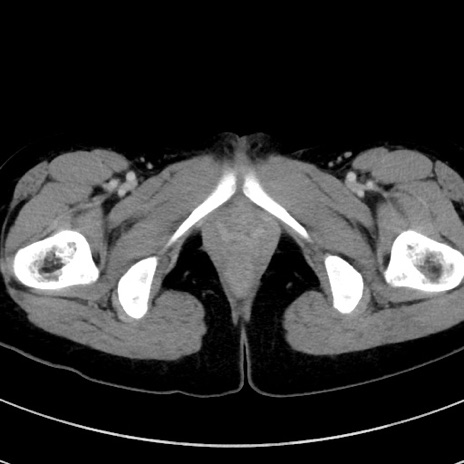

症例17(横断像)

【症例】20歳代女性

【主訴】嘔吐、下腹部痛

【現病歴】昨日夕食後に嘔吐し下腹部痛が出現。本日になっても嘔吐持続し改善しないため来院。

【身体所見】意識清明、BT 37.2℃、BP 108/67mmHg、腹部:平坦、やや硬、下腹部正中から右にかけて圧痛あり、反跳痛軽度あり、tapping pain(+)。

【データ】WBC 13600、CRP 14.94